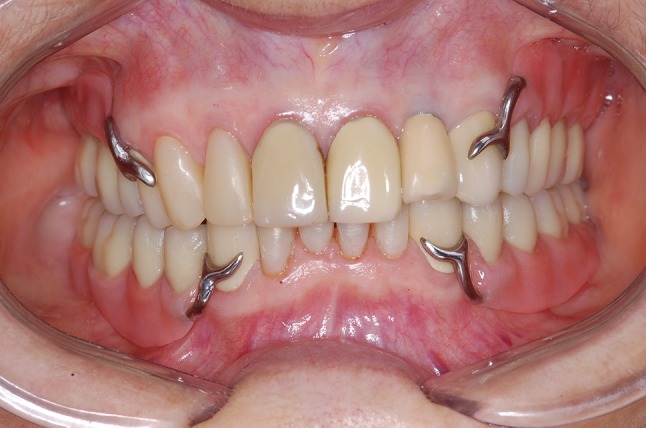

Prior to leaving the dental surgery, the patient was given a hygiene procedure to follow, and provided with instructions on how to remove and insert the prosthesis. A protocol of a periodic review was followed to observe the patient’s adaptation to the RPD. In addition, 14 months after the installation, the prosthesis and the remaining teeth were evaluated clinically, and radiographed (Figs. 8, 9). No resorption around the implants was observed, and there was no requirement for relining of prosthesis. Furthermore, no caries lesions or periodontal diseases were observed. The final outcome presented a satisfactory functionality and esthetic appearance to the patient.

Fig. 8.

Clinical final aspect